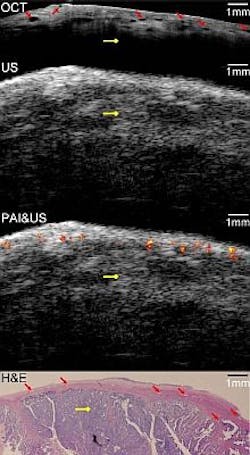

The prototype endoscope created by the developers combines the functionality of photoacoustic imaging, optical coherence tomography (OCT) and pulse-echo ultrasound. It consists of an OCT sample arm probe, a multimode fiber to deliver light for photoacoustic imaging, and a high-frequency ultrasound transducer.

The team tested their device -- described by the team in the September issue of the Optical Society's (OSA) journalBiomedical Optics Express -- by imaging both pig and human ovarian tissue. It correctly identified malignant tumors that were later confirmed by staining the tissue and examining it under a microscope.